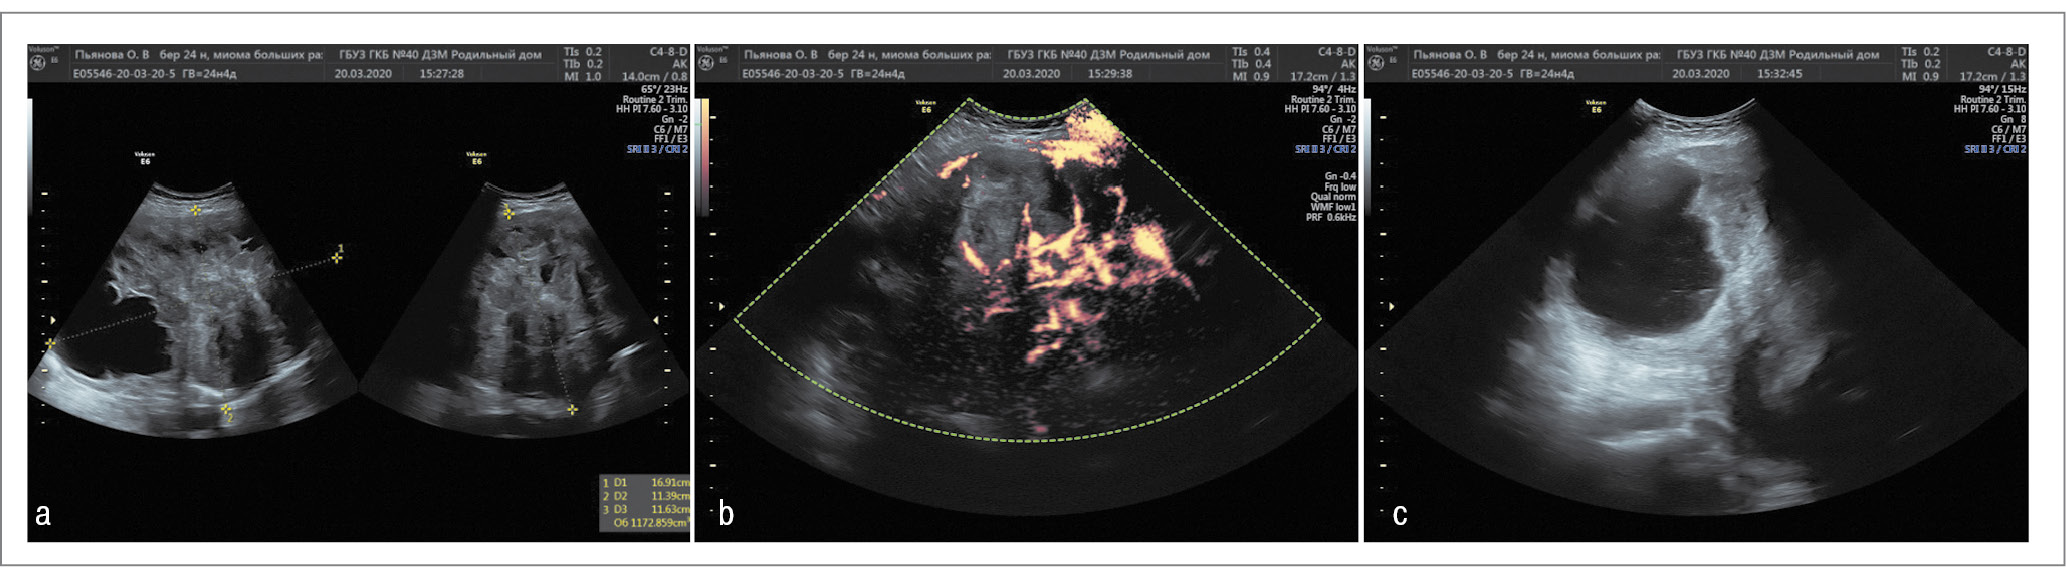

При контрольном УЗИ отмечено увеличение размеров узла до 188×110×156 мм (объем – 370 см3) и кистозной полости до 96×70 мм, содержимое которой приобрело мелкодисперсный характер. Общая структура узла стала пониженной эхогенности, с единичными локусами ЦДК, что свидетельствовало об отеке тканей узла и вторичных изменениях в нем (рис. 2).

Рис. 2. Миома матки в 28 нед беременности: а – миоматозный узел; b – кистозная полость. / Fig. 2. Uterine fibroids (UF) at 28 weeks of pregnancy: a – myomatous node; b – cystic cavity.